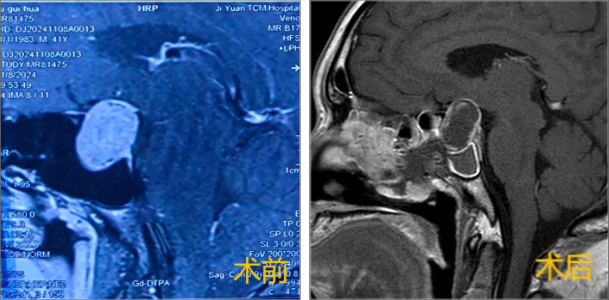

韩某,体检发现生长激素高1周。MRI提示垂体微腺瘤,术前GH:5.69 ng/mL。

肿瘤位于正常垂体左侧,大小约1cm,术中沿假包膜外完整切除,切除后可见正常垂体及左侧海绵窦。术后第一天GH降至0.186 ng/mL,达到治愈标准,术后5天出院。术后1月复查GH:0.063 ng/mL。